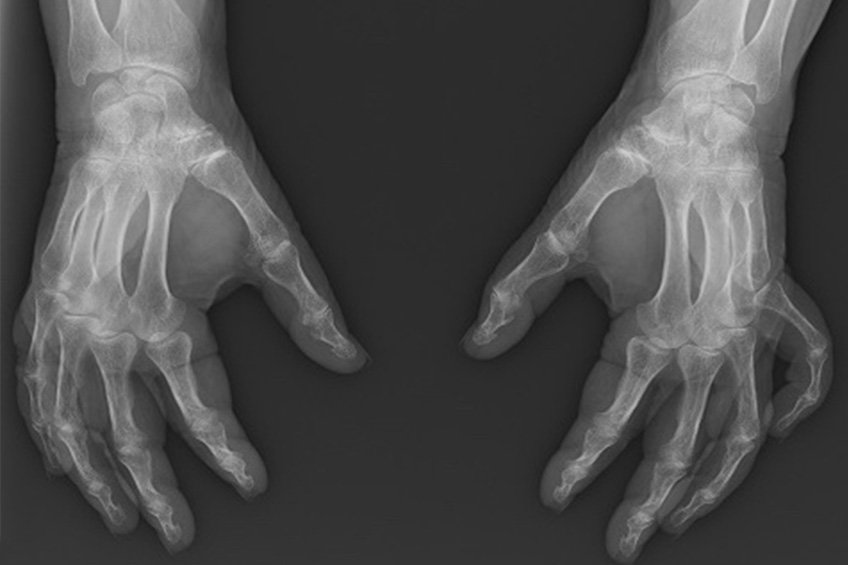

Il s’agit de l’arthrose de la base du pouce, c’est à dire de la destruction progressive des cartilages du trapèze et de la base du premier métacarpien. Elle peut également intéresser d’autres os autour du trapèze.

De simples radiographies permettent de confirmer ce diagnostic pour évaluer l’usure de l’articulation trapèzo métacarpienne.